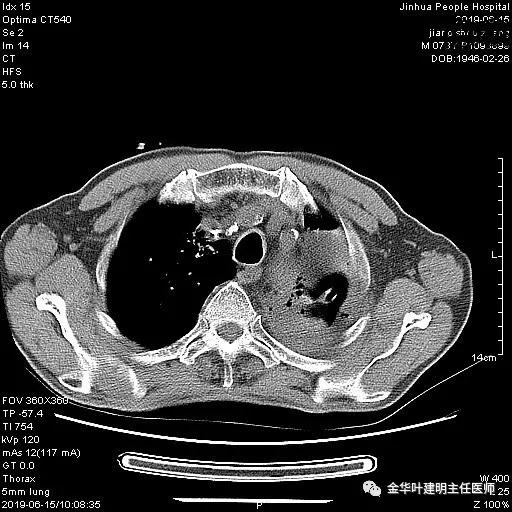

术前检查冠脉CT示:左冠前降支近段多发钙化斑块伴管腔重度狭窄(约85%),建议DSA检查。但追问病史以往平时无胸痛或胸闷症状,运动试验提示可疑阳性(上斜型压低),活动后胸闷气闭症状不明显,既往否认高血压、糖尿病。所以经过心内科会诊讨论,认为还是可以进行手术。术前冠状动脉CT示:

6.15上午:24小时胸管引流出血性液250ml;复查胸部CT示: